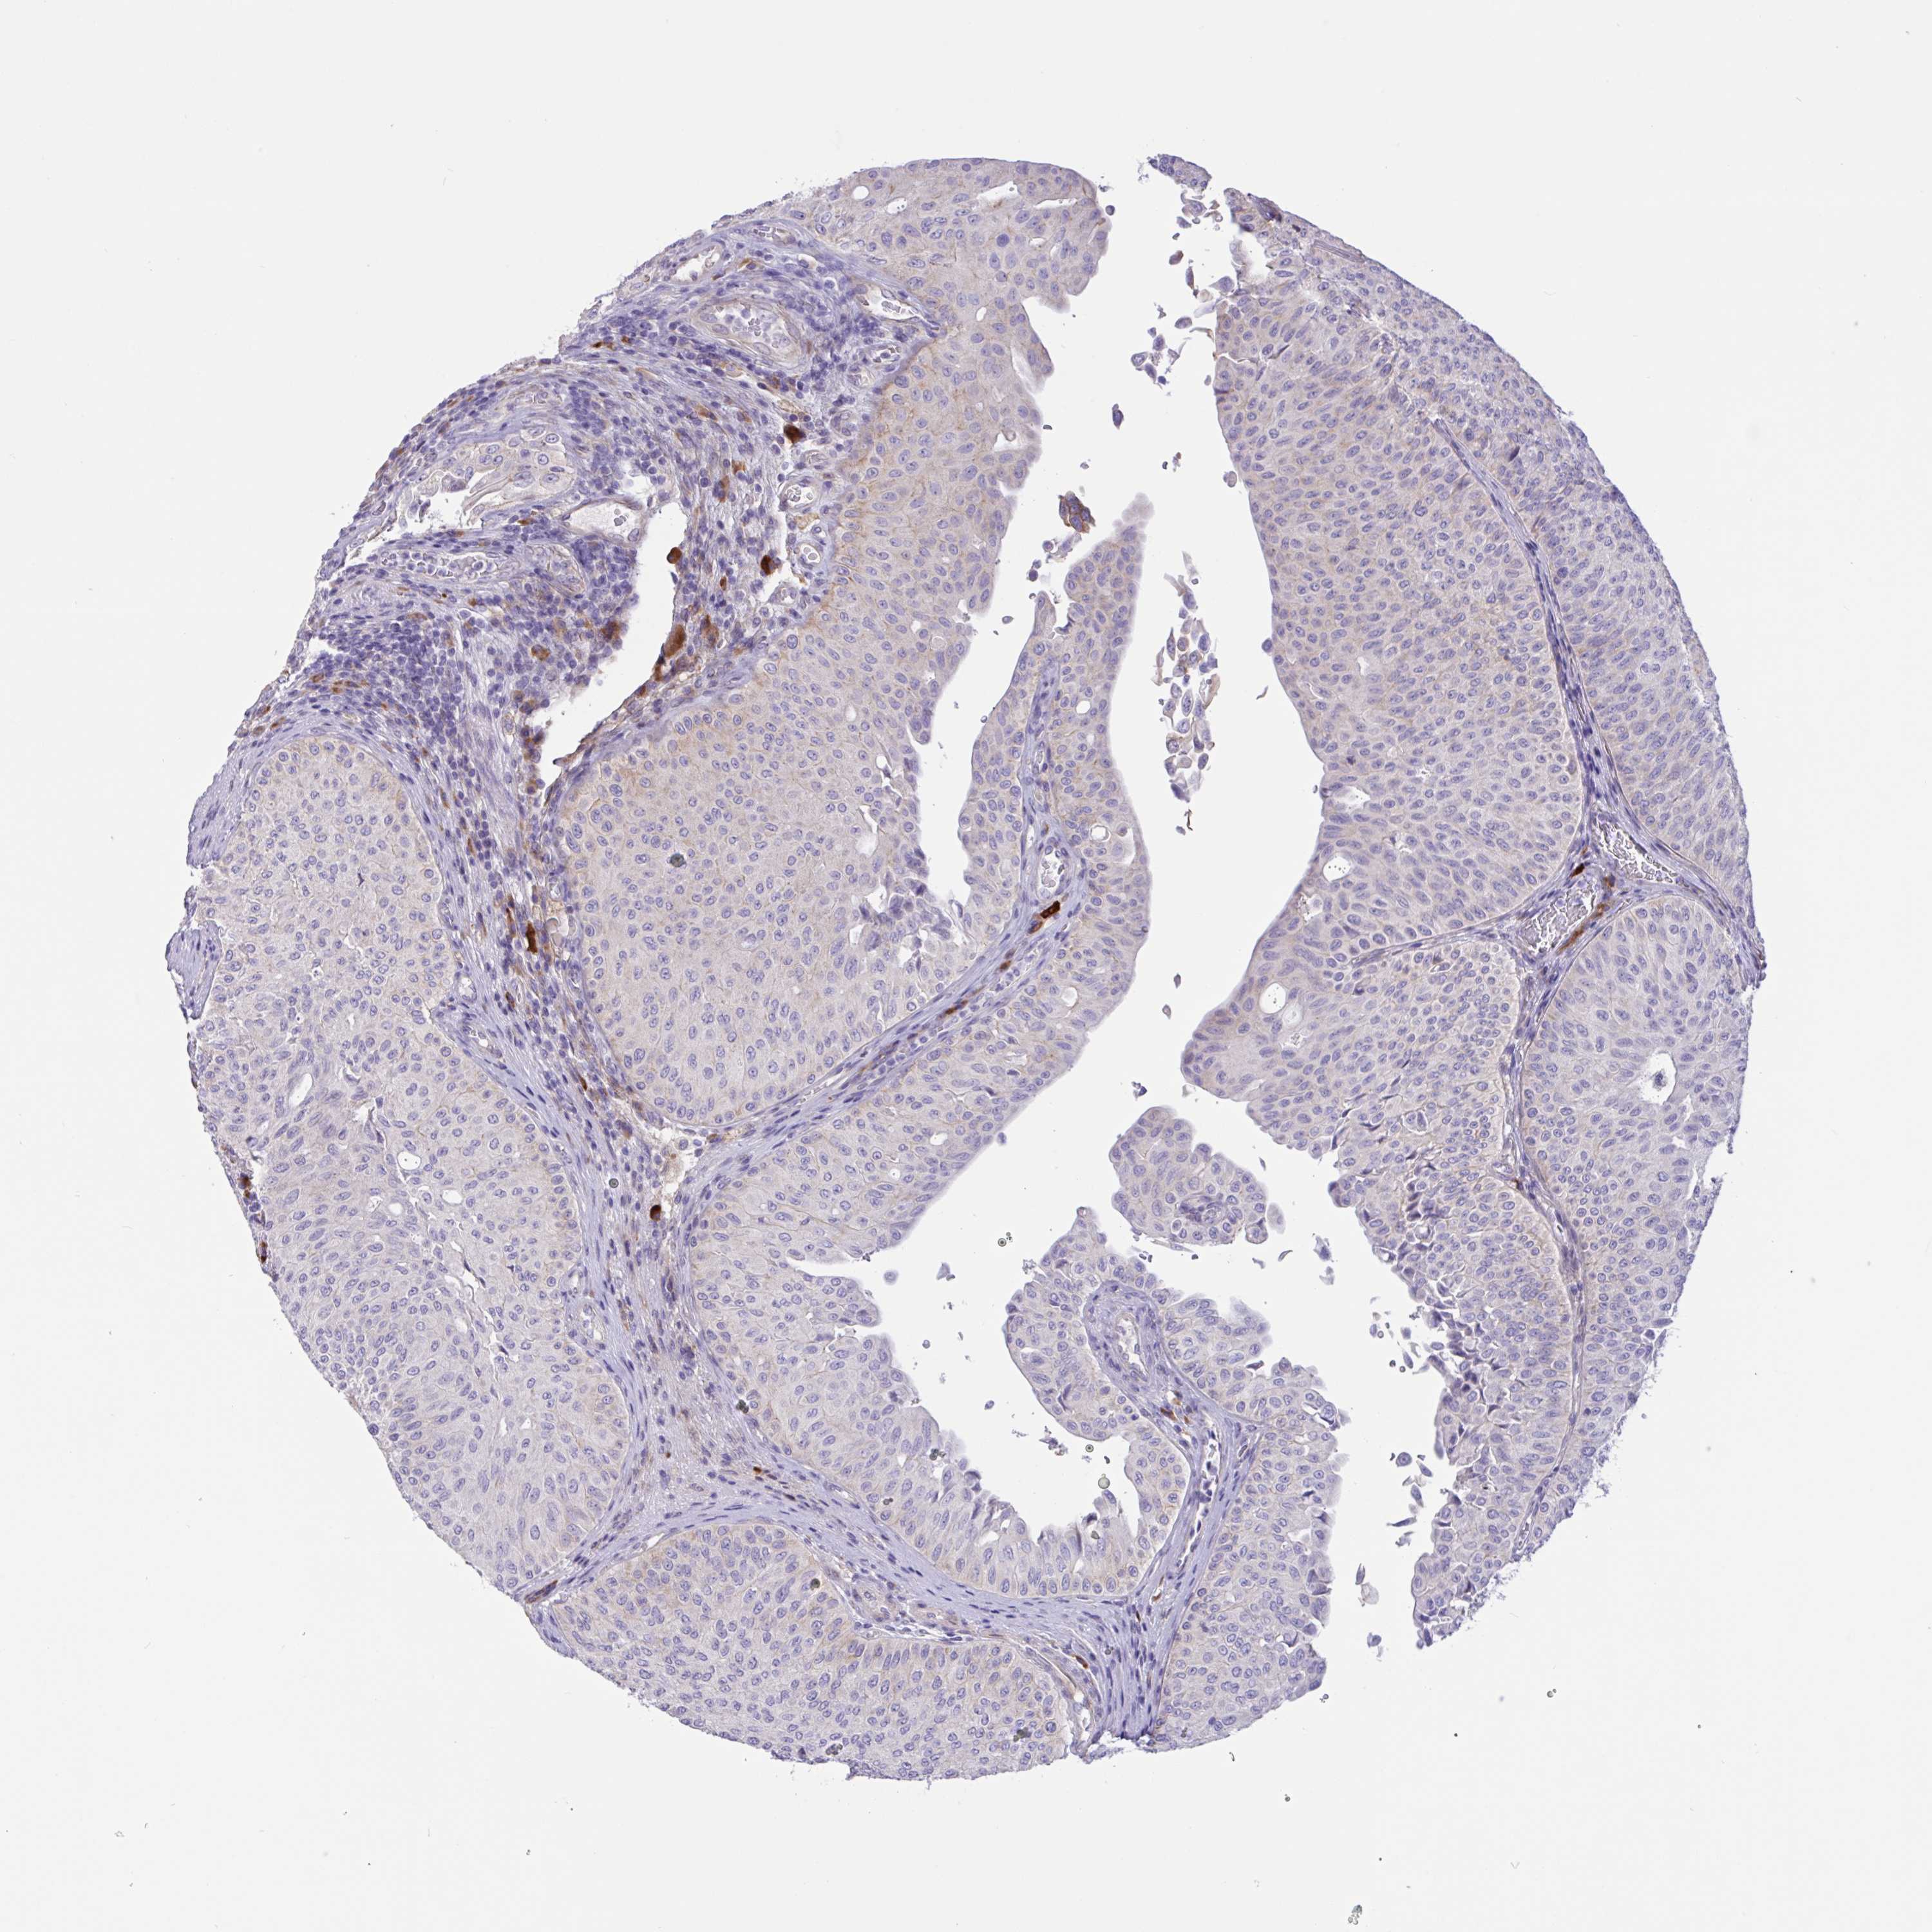

UROTHELIAL CANCER - Protein expressioni

A mouse-over function shows sample information and annotation data. Click on an image to view it in a full screen mode. Samples can be filtered based on level of antibody staining by selecting one or several of the following categories: high, medium, low and not detected. The assay and annotation is described here.

Antibody stainingi

Antibody staining in the annotated cell types in the current human tissue is reported as not detected, low, medium, or high, based on conventional immunohistochemistry profiling in selected tissues. This score is based on the combination of the staining intensity and fraction of stained cells.

Each image is clickable and will lead to virtual microscopy that enables deeper exploration of all samples and also displays staining intensity scores, fraction scores and subcellular localization as well as patient and tissue information for each sample.

Antibody HPA049265

Antibody CAB037328

Urothelial carcinoma, High grade

Urothelial carcinoma, Low grade

Urothelial carcinoma, NOS